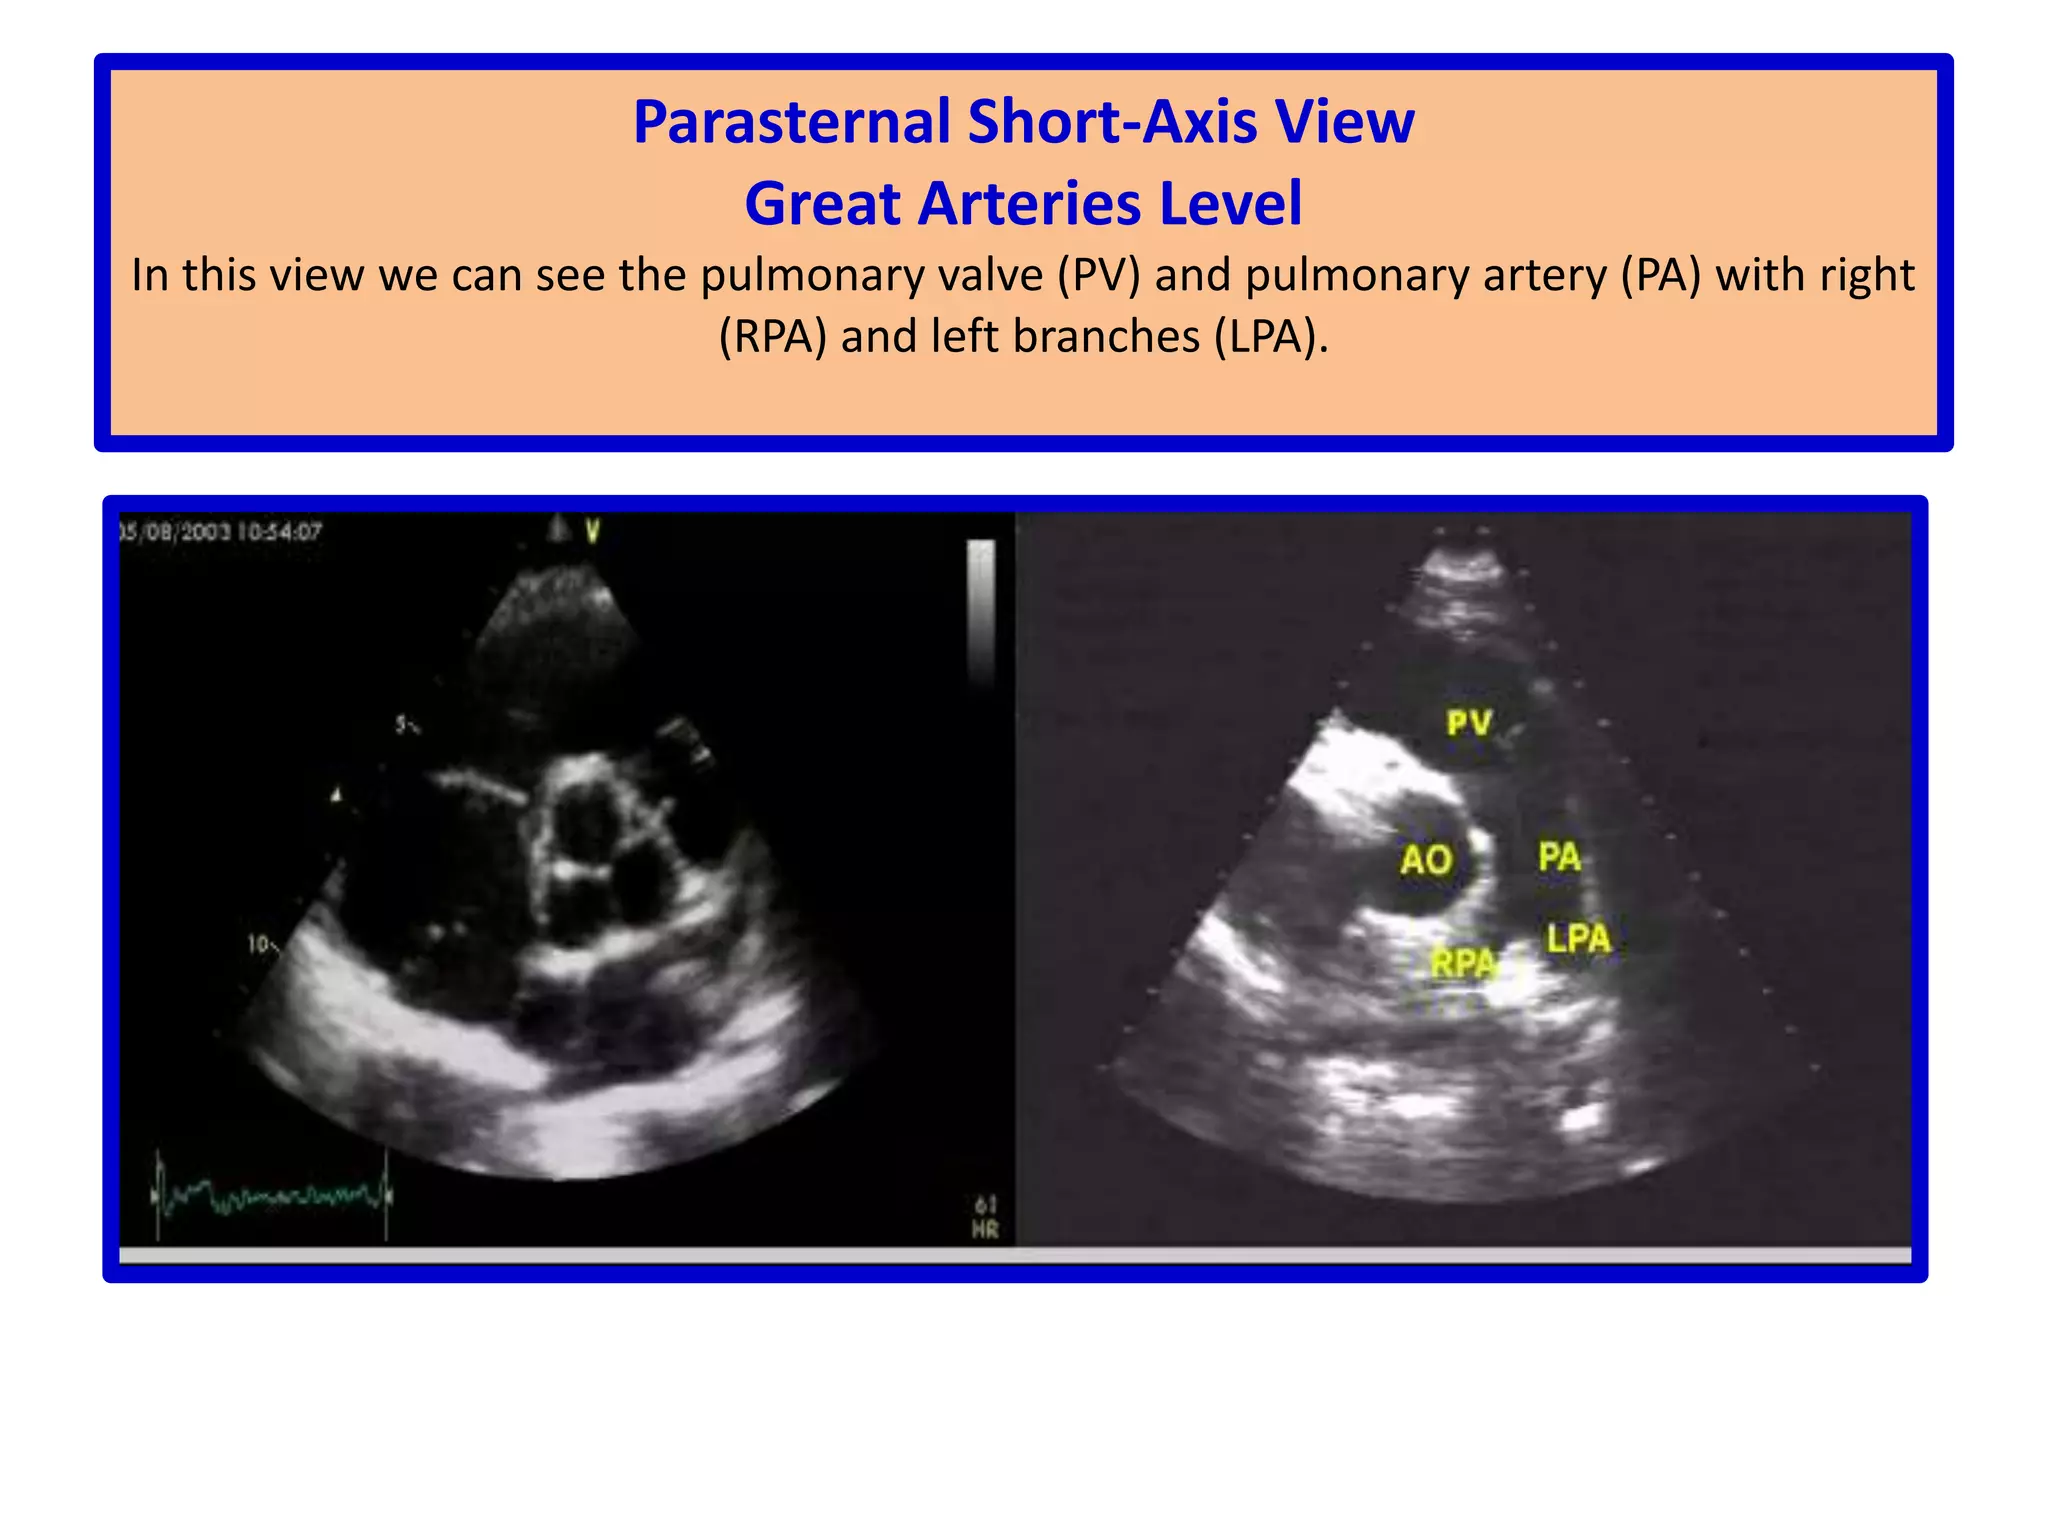

Parasternal Short-Axis ViewGreat Arteries LevelIn this view we can see the pulmonary valve (PV) and pulmonary artery (PA) with right (RPA) and left branches (LPA).

Parasternal Short-Axis ViewGreatArteries LevelIn this view we can see the pulmonary valve (PV) and pulmonary artery (PA) with right (RPA) and left branches (LPA).